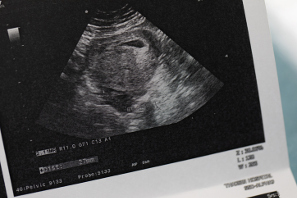

A lo largo de la gestación, el organismo de la embarazada sufre muchos cambios, por dentro y por fuera, dando lugar a síntomas de embarazo muy característicos. No es solo que crezca la tripa porque dentro se está formando un bebé. Las modificaciones van mucho más allá: la naturaleza altera el cuerpo de la mujer para preparar el parto y para la crianza del bebé. Y los síntomas que aparecen en el embarazo tienen su origen en esa adaptación. Los primeros síntomas que aparecen, para que tu organismo “acepte” al bebé que crece dentro de ti, y los posteriores para pueda nacer y luego alimentarse. Toda esta sintomatología tiene sus propias curiosidades y rarezas. ¿Quieres conocerlas? Sigue leyendo.